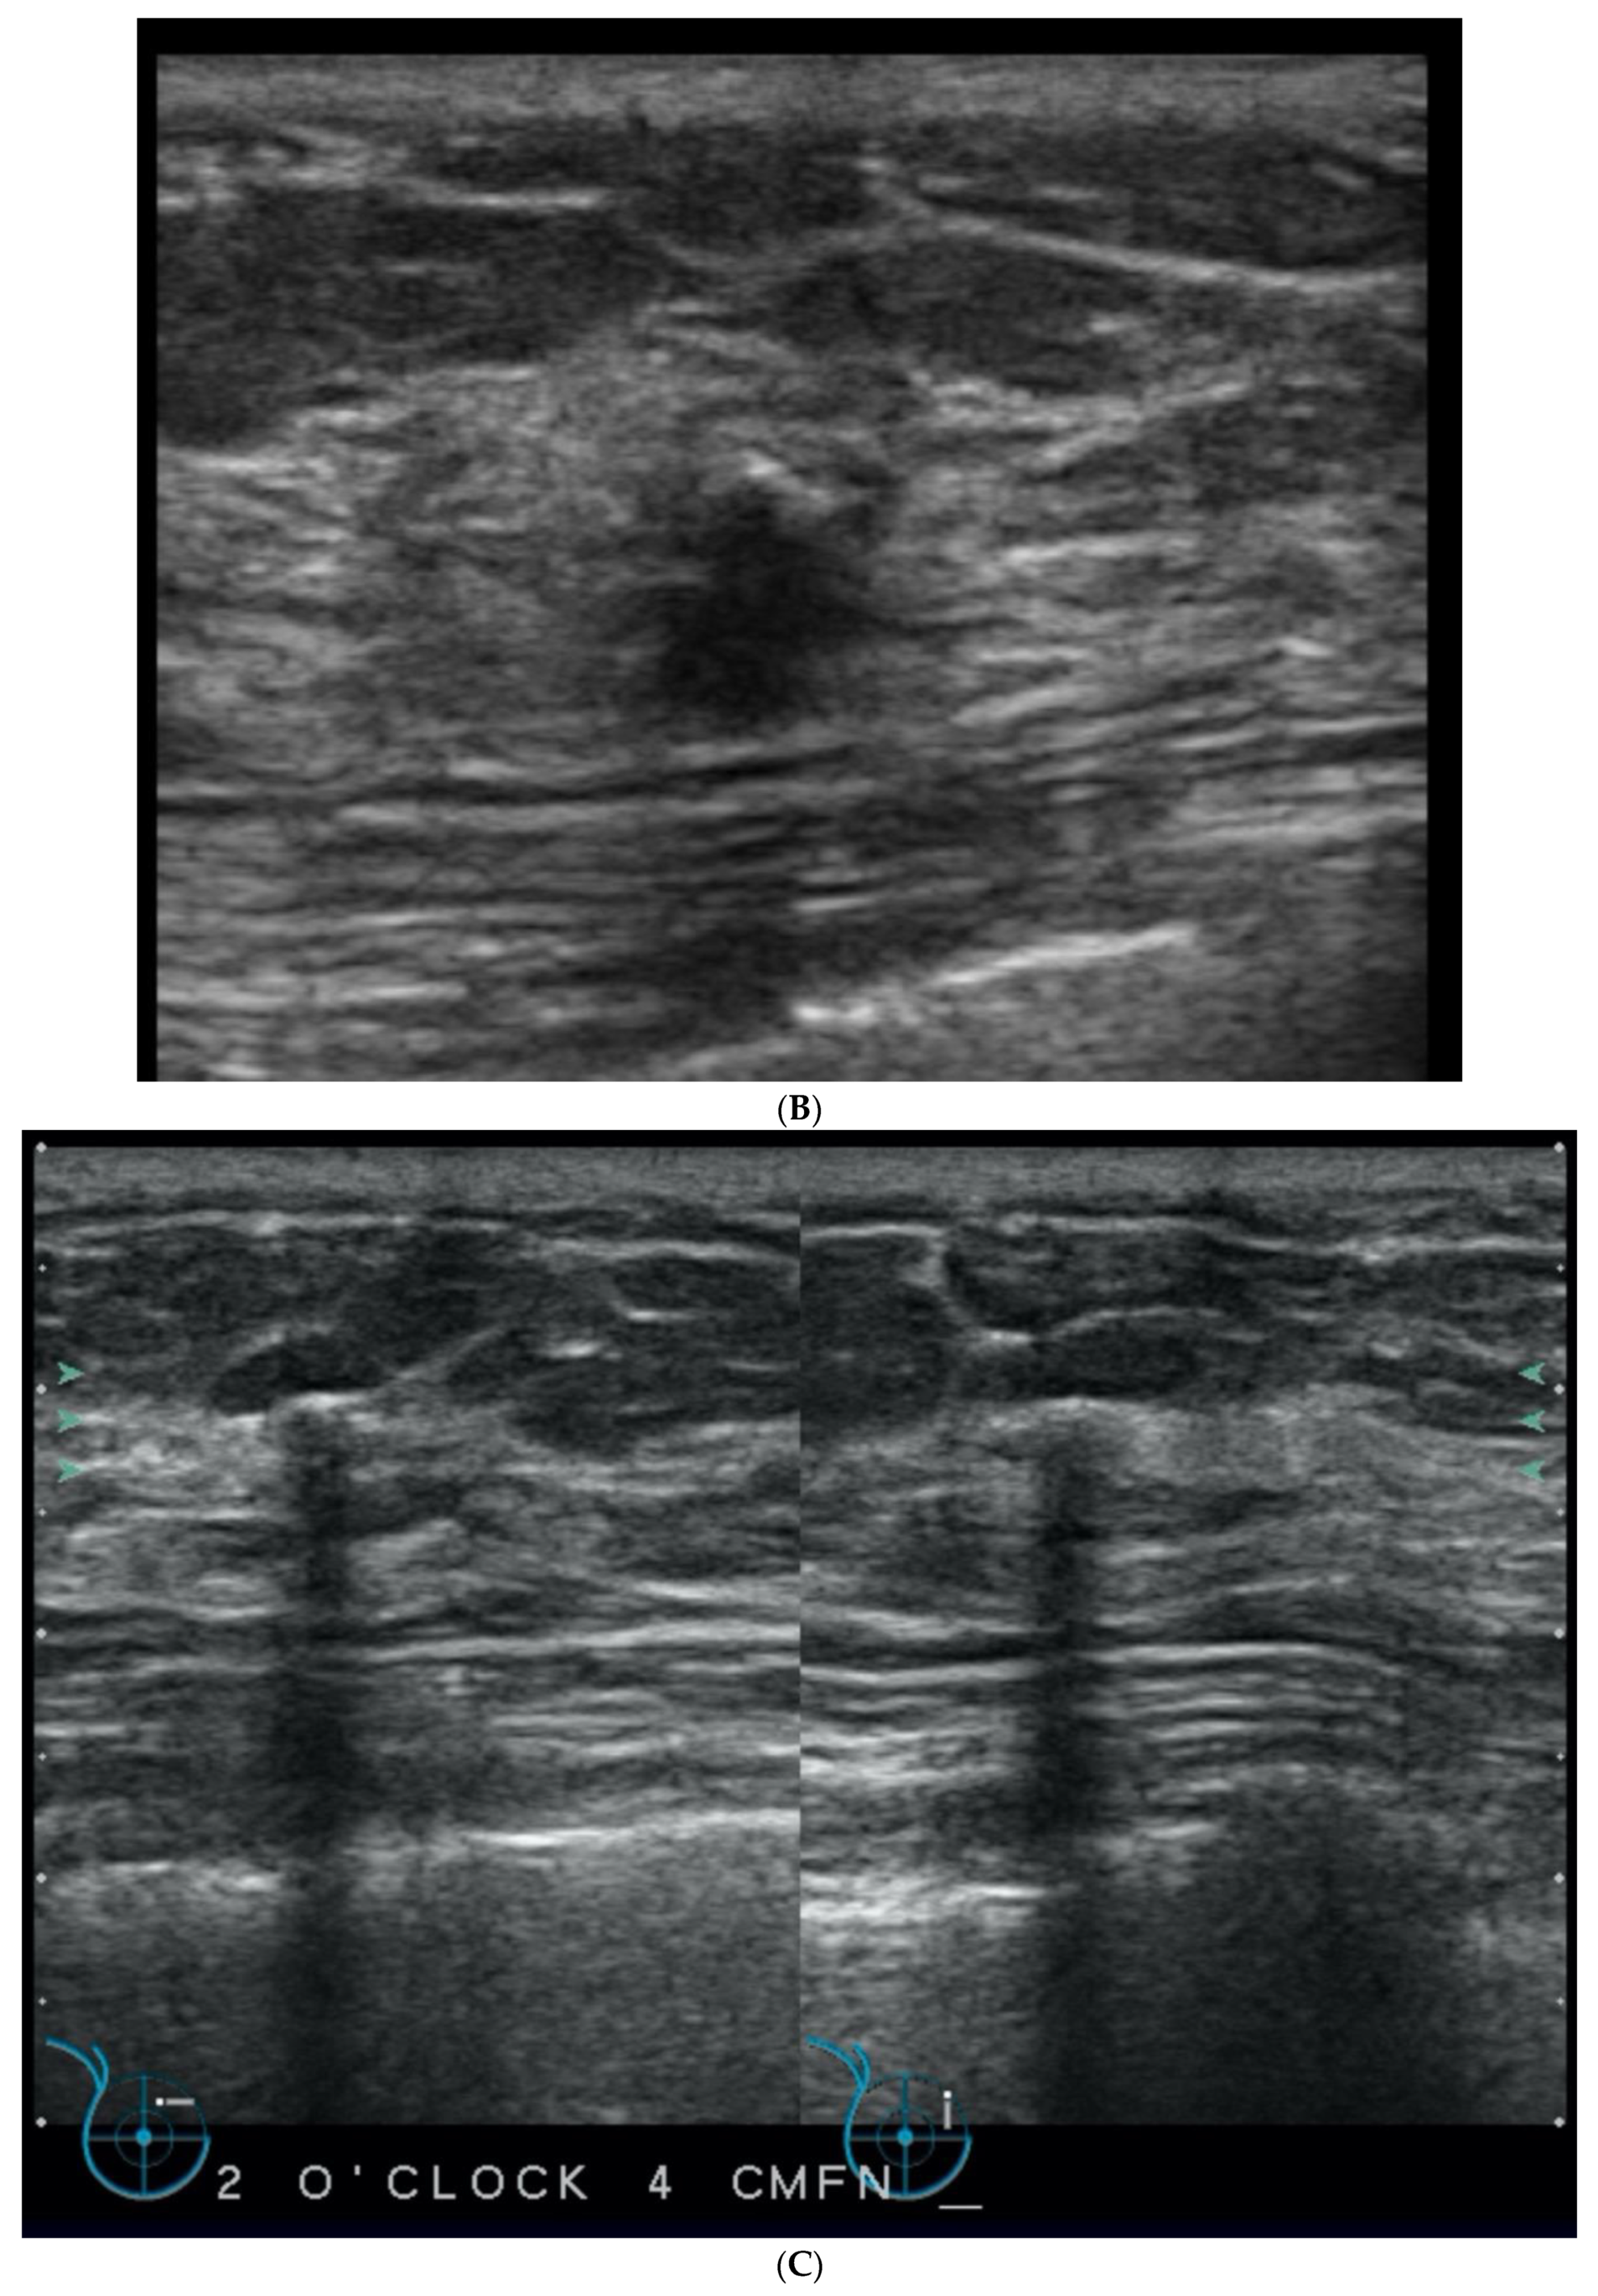

5. Ultrasound (US)